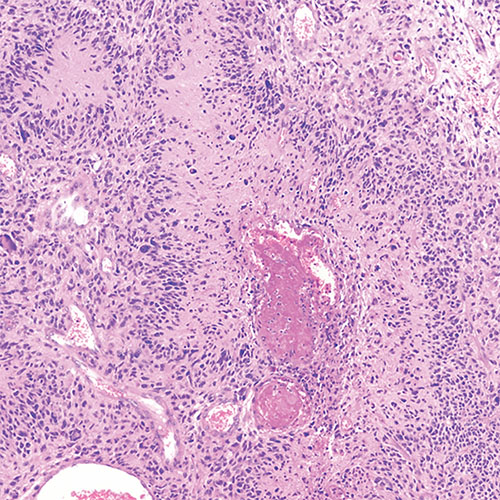

Glioblastoma is the most common and, unfortunately, the most malignant tumor that starts within the brain itself. Glioblastoma tumor cells spread throughout the brain so that complete surgical removal is not possible. Radiation and chemotherapy are used to slow the spread of the tumor; they do not cure the condition. More than 12,000 people are diagnosed with glioblastomas in the United States every year.

Glioblastoma under a microscope.

Glioblastoma